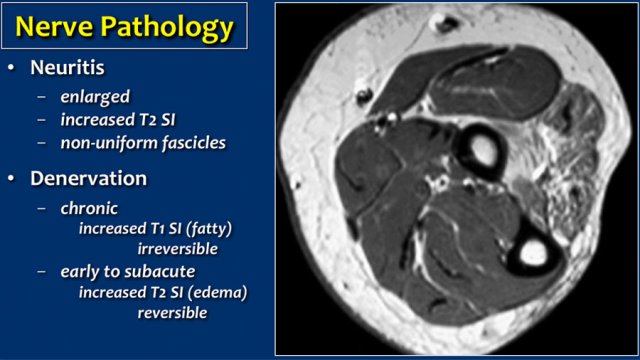

Denervation

Nerve pathology can present as thickening of the nerve when there is neuritis or as a result of compression of the nerve.

A secondary sign of nerve pathology is denervationwith edema and/or atrophy of the muscle.

In this case there is chronic atrophy with high sinal on T1, which is irreversible.

In early or subacute denervation the prominent sign is edema with high signal on T2W-images and that is reversible.